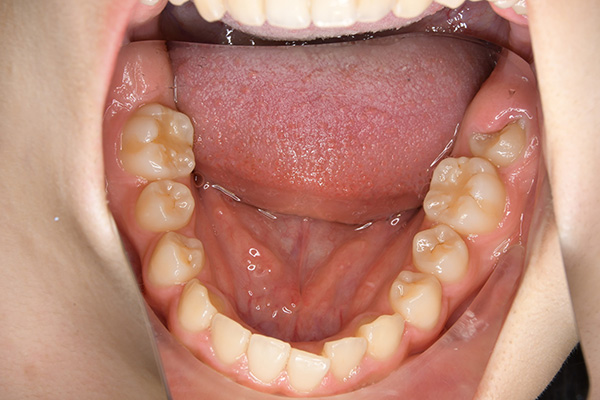

経過観察(13歳10ヵ月)

経過観察

(13歳10ヵ月)

批評・予后 上顎前歯のアライメントを行ったことで、ロッキングされていた上顎歯槽基底骨の成長に良い影響が生じており、側方歯群の交換も順調に進んでいる症例である。2期治療は相談の上、希望があれば行うこととしている。